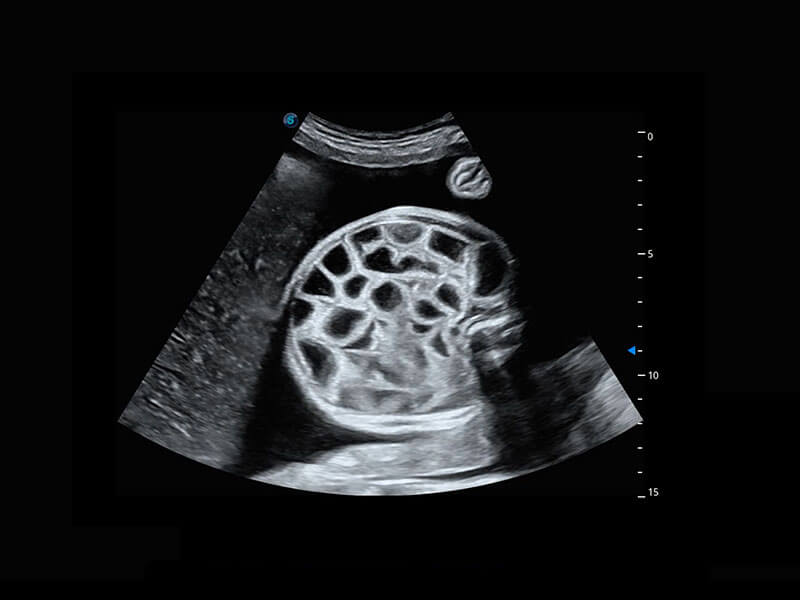

中晚孕筛查

P60提供简单易学易用的高端诊断工具,为您中晚孕筛查提供快速清晰的解剖信息。

1 OFD(HC): 87.03 mm

HC: 251.00 mm

GA: 27w 1d

HC/AC: 96.13 %

2 BPD: 70.56 mm

GA: 28 w 2d

S-Fetus(acq.)

& S-Fetus(meas.)

S-Fetus

S-Fetus能够助您在实时扫查过程中自动识别标准切面、自动测量并录入报告。一个按键,即可快速、高效地获取胎儿生理指标,简化您的产科检查操作。